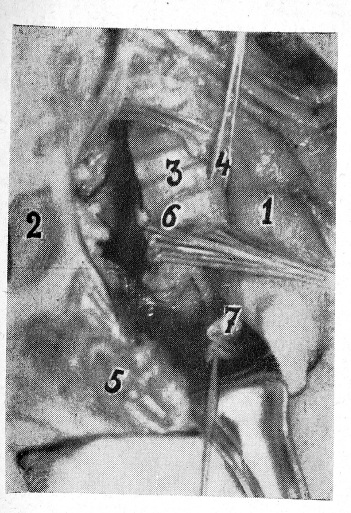

Доступ к центральному отделу правого главного бронха. Грудину и перикард рассекают продольно. При рассечении перикарда надо помнить, что в области рукоятки грудины над верхним краем перикарда под слоем клетчатки лежит левая плечеголовная вена. Восходящую аорту крючком отводят от верхней полой вены, вследствие чего возникает аорто-кавальный промежуток. В нем следует ориентироваться на контур правой легочной артерии, расположенной поперек промежутка на 1,5—2,0 см выше правого предсердия. В верхнем перикардиальном кармане можно через задний листок перикарда прощупать правый край трахеи, а в нижнем на участке правого отверстия поперечного синуса — бифуркацию трахеи. Задний листок перикарда надсекают выше контура правой легочной артерии продольно, а ниже контура — поперек (помнить, что здесь купол правого предсердия). Под правую легочную артерию проводят диссектор, артерию выделяют, перевязывают (или прошивают аппаратом) и пересекают. Возникает довольно значительная перикардиальная операционная рана. Рассекают претрахеальную клетчатку, выявляют правый трахеобронхиальный угол, рассекают фасциальный футляр трахеи и правого бронха. Последний легко выделяют, накладывают аппарат УКБ, пересекают бронх у трахеи и прошивают (рис. 3). Иссекают периферическую культю.

Рис. 3. Средний сердечно-перикардиальный промежуток (аорто-кавальный). Ручное ушивание пересеченного у трахеи правого главного бронха:

1 восходящая аорта; 2 — верхняя полая вена: 3 — трахея; 4 — подведена лигатура под левый главный бронх; 5 — правое предсердие с правым ушком; 6 — ушивание пересеченного начального отдела правого главного бронха; 7 — пересечен и перевязан центральный конец правой легочной артерии, периферическая часть также перевязана и ушла под верхнюю полую вену. Периферическая часть культи правого бронха обработана и иссечена.